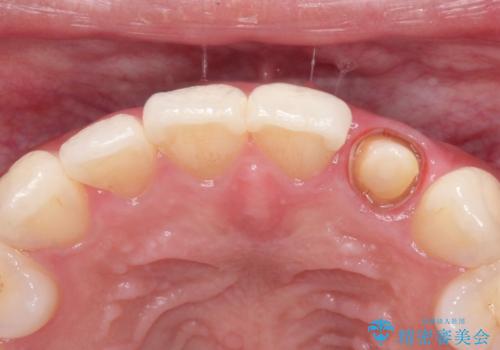

前歯の変色 オールセラミッククラウン

- 前歯の変色を主訴に来院されました。

根管治療後、オールセラミッククラウン(エクセレント)にて治療を行なっています。